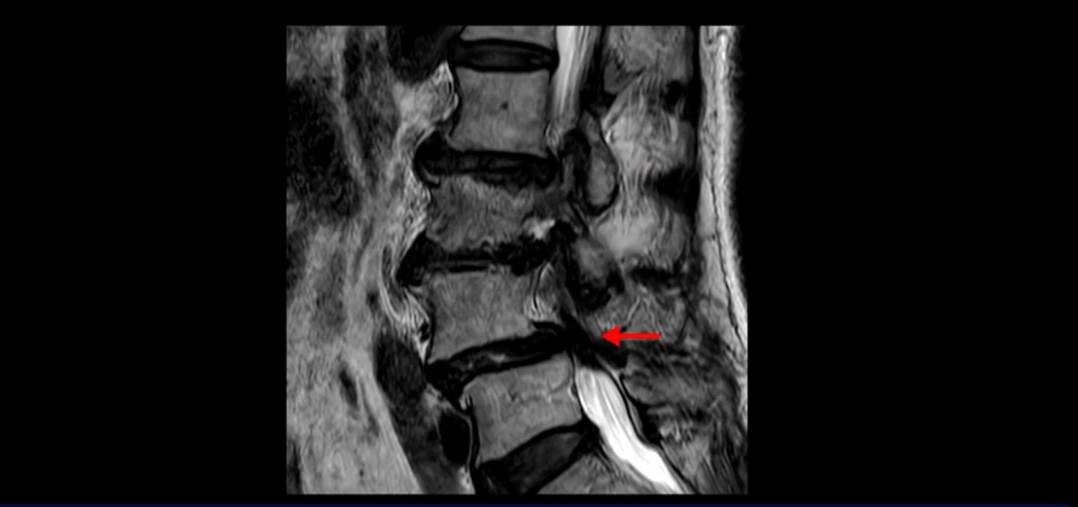

또 척추관협착도 매우 심합니다.

척추관이 심하게 좁아져 있습니다.

이렇게 여러 마디가 안 좋고 뼈도 밀려 나가 있으니까 나사박는 수술해야 하는데, 대학병원에서도 수술을 한 번에 못 하고 두 번에 나눠서 해야 한다고 들으셨습니다. 왼쪽으로 신경가지가 빠져나가는 추간공도 많이 좁아져 있습니다.

이렇게 신경 구멍들이 좁아져 있고 신경이 눌리니까 엉덩이와 다리가 너무 저리고 아파서 아예 일어서질 못하니까 휠체어를 타고 병원에 내원하셨는데요. 그럼 어떻게 이분처럼 신경이 눌려있는 환자분들을 수술 없이 치료해서 잘 걷게 만들고 엉덩이와 다리가 저리고 아픈 증상이 사라지게 할까요? 지금부터 설명해 드립니다.